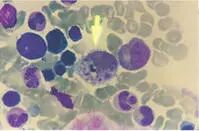

流行性出血热,国际又称肾综合症出血热,是一种经鼠传播、由汉坦病毒引起的,临床上以发热、出血和肾损害为主要特征的严重的急性传染病。在我国属于乙类传染病。

人感染汉坦病毒后潜伏期通常为7-14天,也偶见短至4天或长至2个月者。典型临床表现具有三大主征,即发热、出血和肾损害。

患者起病急,早期有发冷,发热等症状,全身酸痛,乏力,呈衰竭状;

可有头痛,眼眶痛,腰痛(三痛)和面、颈、上胸部充血潮红(三红),呈酒醉貌;

可出现眼睑浮肿、结膜充血,水肿,有点状或片状出血;

上腭粘膜呈网状充血,点状出血和腋下皮肤有线状或簇状排列的出血点。患者束臂试验阳性。

典型病例病程经过有发热期、低血压休克期、少尿期、多尿期和恢复期五期经过。